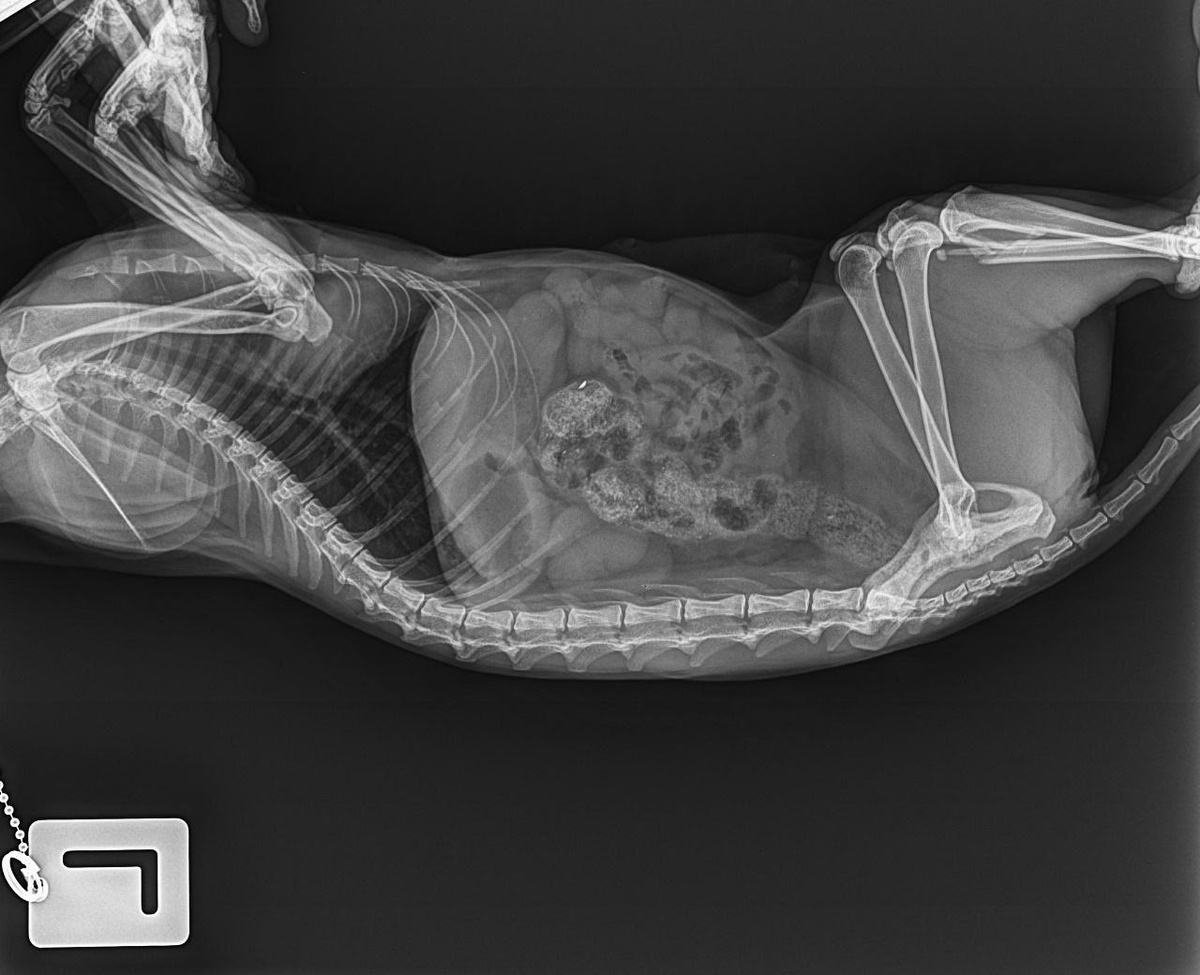

Ситуация такая: у знакомой девочки (она учится в 9 классе, сирота, живет с бабушкой) машина сбила кошку. Сегодня ездили на рентген. Диагноз: раздроблена задняя лапа, но, к счастью, всё остальное цело.

Я нашла клинику, где ей готовы сделать операцию за 10 000 рублей. Врач предупредила, что дольше недели ждать нельзя — может начаться воспаление, так как осколок впивается в мышцу. Пока явного воспаления нет, температура в норме, но кошка отказывается от еды.